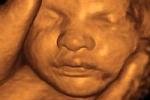

Частная британская клиника Portland Hospital, открывшая роддом, предложила женщинам сервис по трехмерному ультразвуковому сканированию зародыша.

Полученные высококачественные изображения и видеофайлы будущие мамы смогут скачать со специального сайта и поместить в переносные устройства вроде плееров iPod или мобильных телефонов.

Для создания трехмерного изображения зародыша достаточно сорокаминутного сканирования. Стоимость процедуры в данной клинике не называется, но обычно находится в диапазоне от 140 до 250 фунтов стерлингов (от 280 до 500 долларов США).